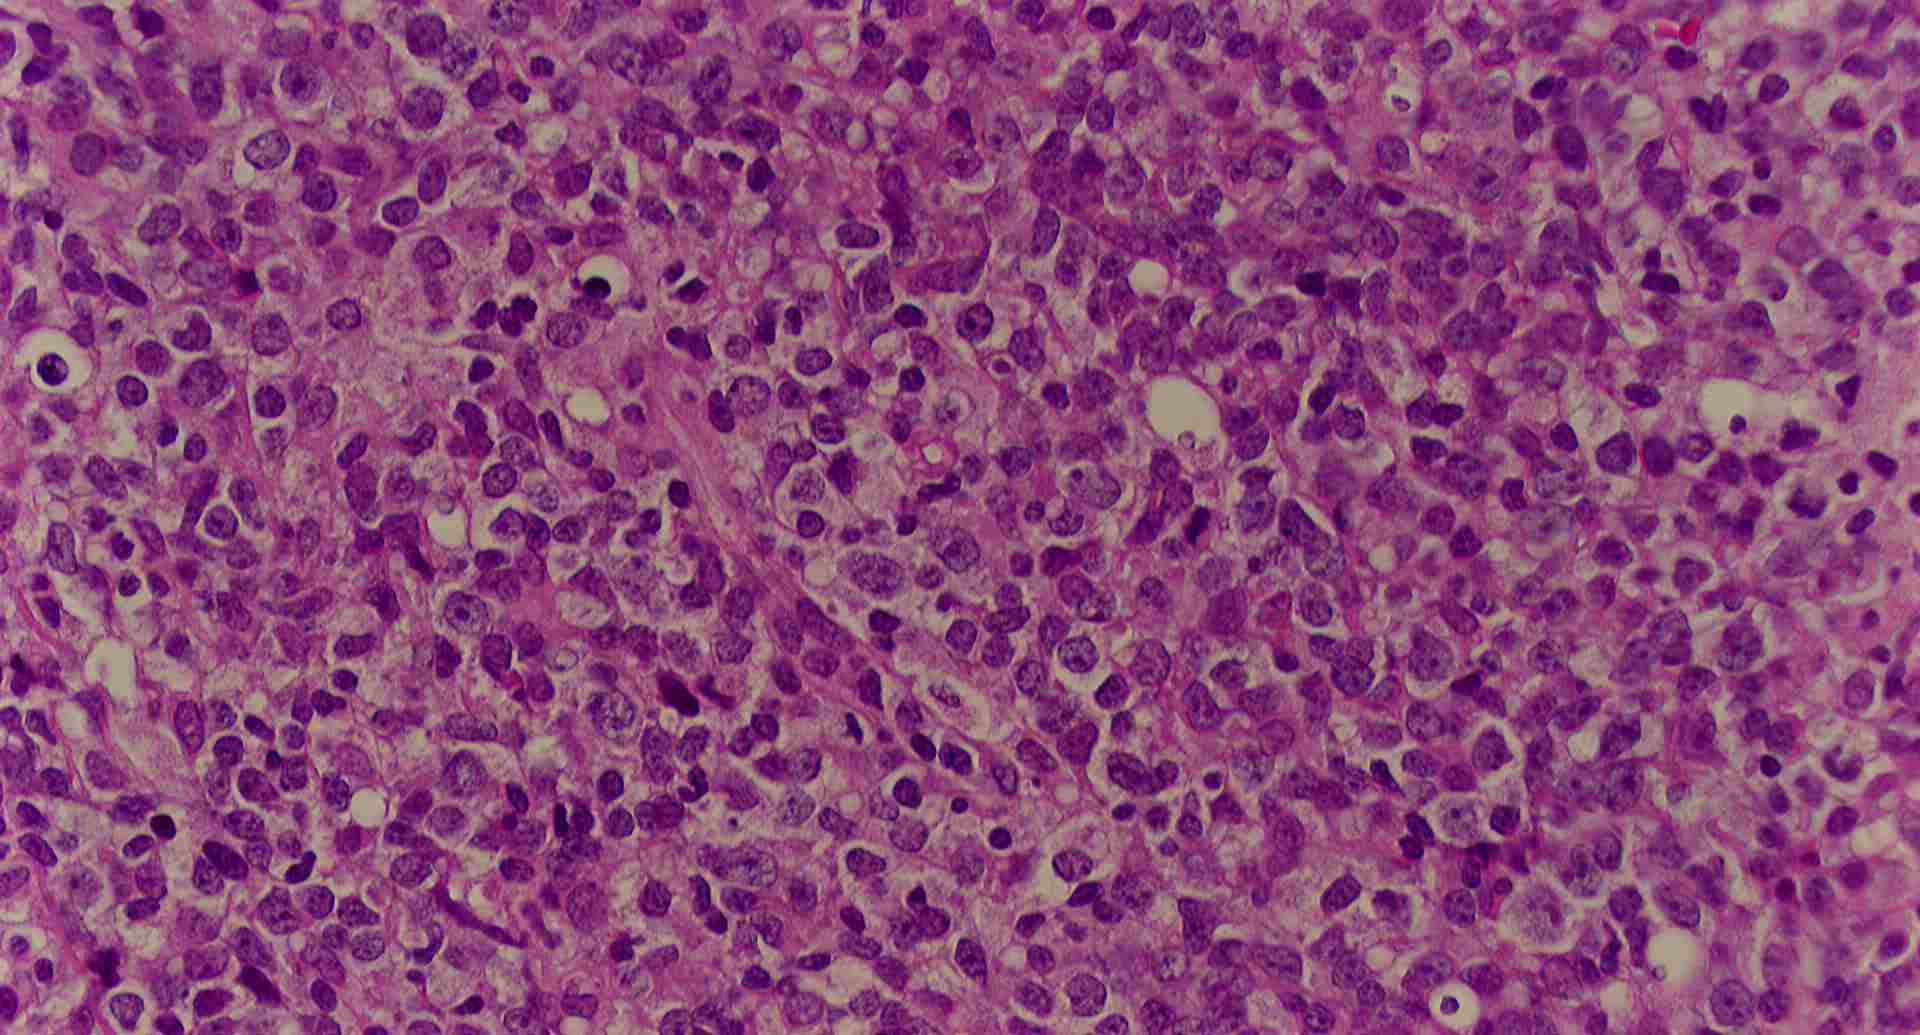

標本1

sample